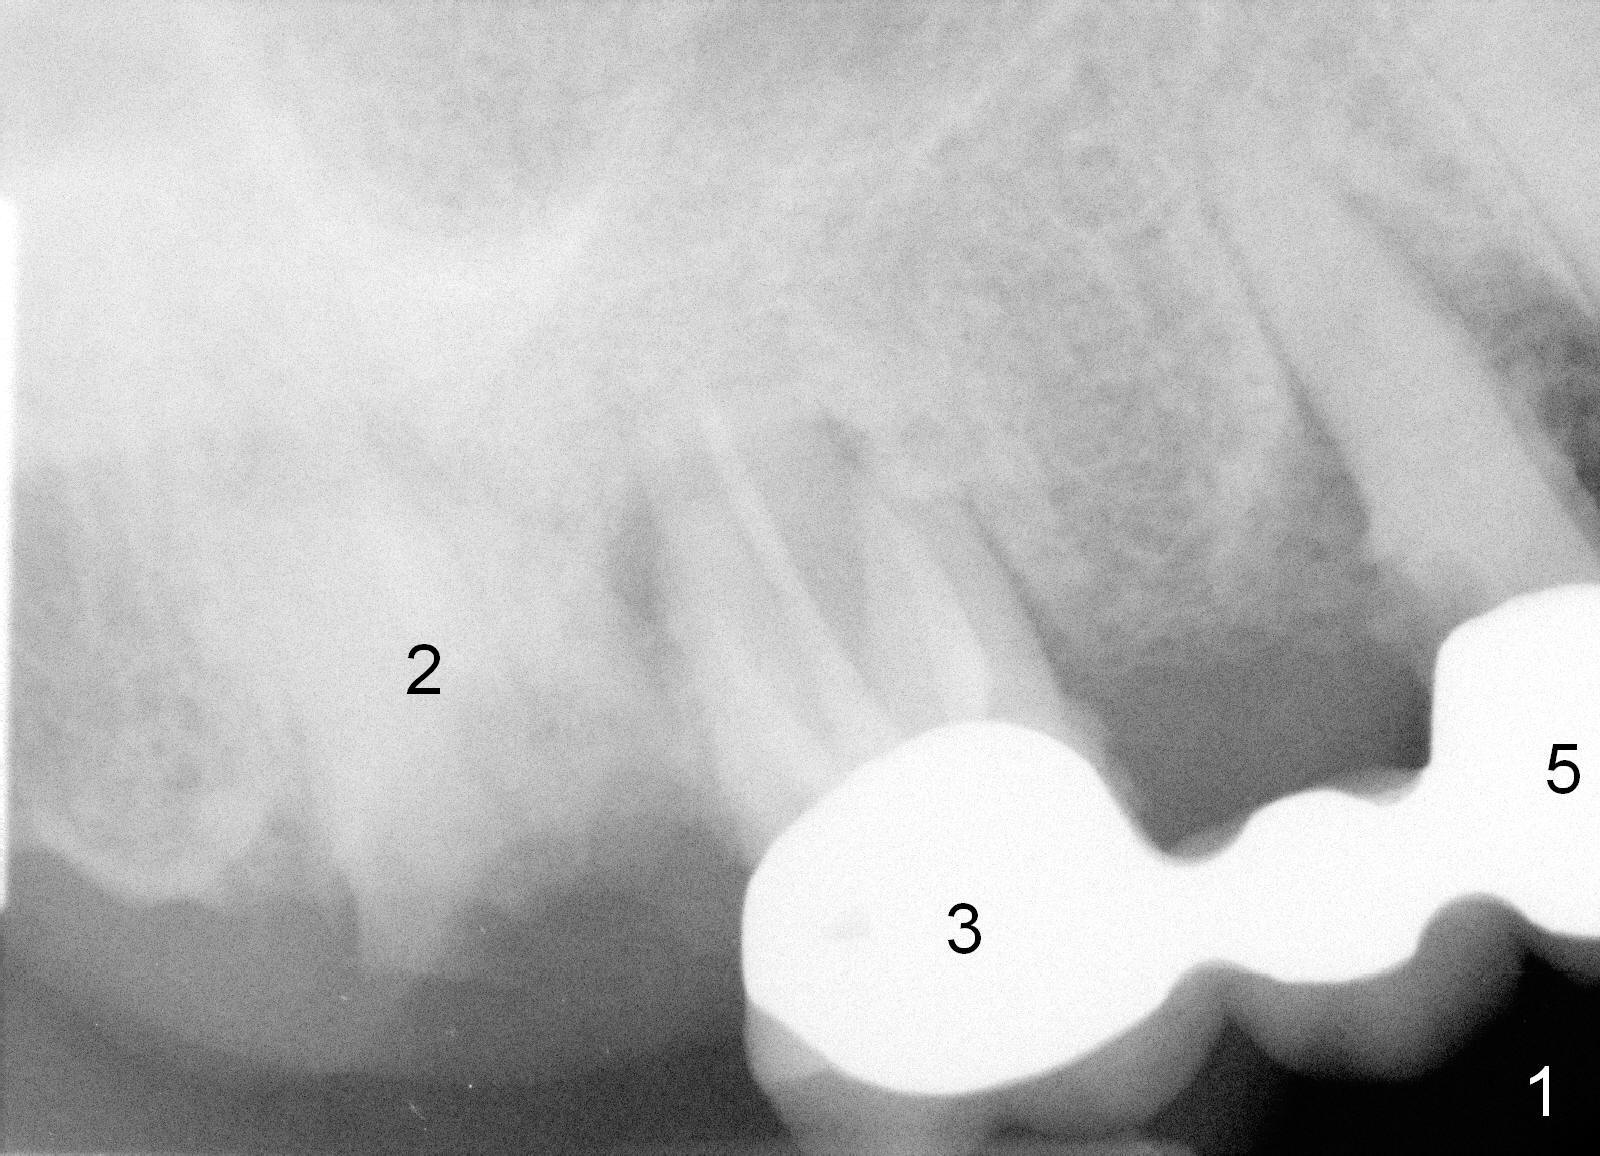

A 78-year-old lady (YT) has had poor dentition.  The tooth #2 fractured 3 years ago (Fig.1).  Now bone loss around the abutments for the bridge at #3-5 is more severe (Fig.2).  There is an abscess palatal to the tooth #5.  After extraction, the socket at #3 should be large (treated with 2% Xylocaine/1:50,000 Epinephrine).  An extra wide implant is expected.  Since there is more than 12 mm of bone in height (Fig.3), a UF implant is the most appropriate (6, 6.5 or 7x12 mm, Fig.4).  The longest extra wide SM implant is 10 mm.